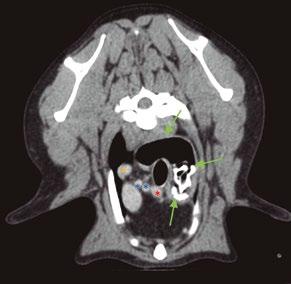

En la exploración general se observó baja condición corporal, leve grado de deshidratación y linfadenomegalia del ganglio poplíteo derecho.

La exploración dermatológica reveló la presencia de una lesión erosivoulcerativa con solución de continuidad en la zona dorsal del tarso de la extremidad posterior derecha. Los bordes de la lesión se presentaban indurados y la zona central con un exudado seroso (figura 1). Asimismo, se apreció pelo ralo y xerosis generalizada.